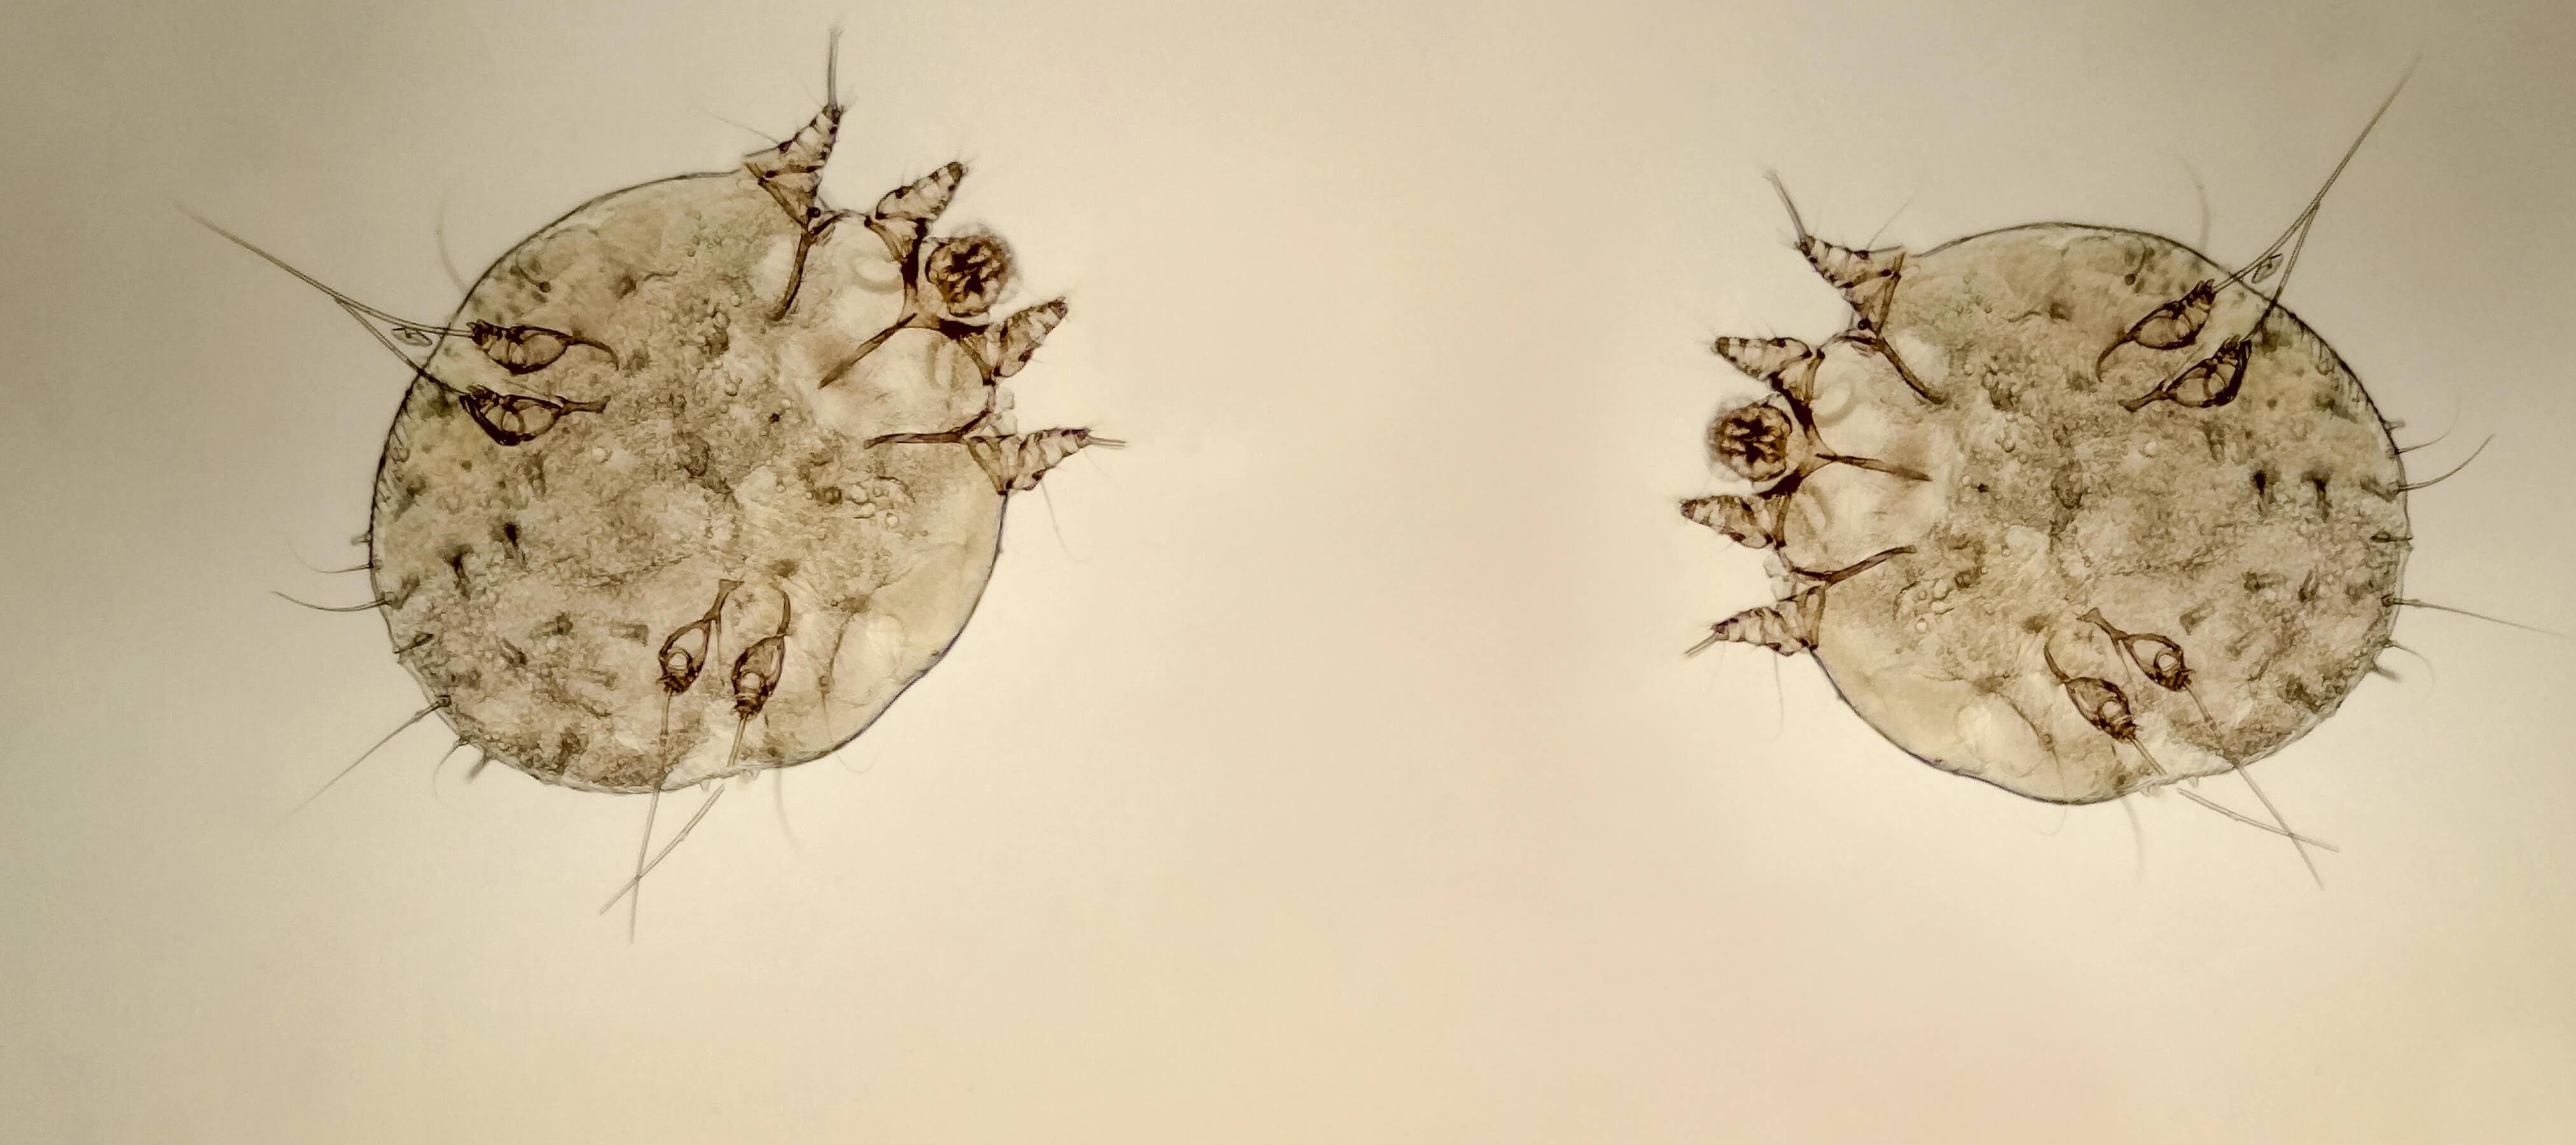

1994'ten beri Sakarya’da Dermatoloji (Cildiye) Uzmanı olarak çalışan Dr. Ahmet Acar 39 yıllık meslek hayatı boyunca üniversite, devlet hastanesi, özel muayenehane hekimliği tecrübelerinin sağladığı birikimle hizmetlerine devam ederken tüm deri hastalıkları ve zührevi hastalıkların tedavilerini gerçekleştirmektedir. Bununla birlikte yüz gençleştirme, estetik lazer yöntemleri, cilt bakımları ve HPV tedavileri en çok hizmet verdiği alanlardır.